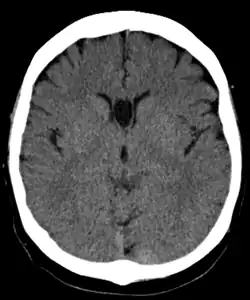

Полость прозрачной перегородки (лат. cavum septi pellucidi) — полость, находящаяся между листками прозрачной перегородки. Полость содержит ликвор, попадающий туда через поры в листках.[1]

Спереди полость ограничена коленом мозолистого тела; сверху — стволом мозолистого тела; сзади — передними ножками и столбами свода мозга; снизу — передней комиссурой и клювом мозолистого тела; латерально — листками прозрачной перегородки.[2]

В большинстве случаев полость не сообщается с полостью желудочковой системы мозга, что делает неправомочным её описание как «5-го желудочка» головного мозга, тем не менее, иногда её называют пятым желудочком.

Собственно полость прозрачной перегородки расположена на уровне основания передних рогов боковых желудочков мозга, а её распространение в заднем направлении в область тел боковых желудочков выделяют под названием полость Верге (лат. cavum vergae). Во время эмбрионального развития происходит закрытие полостей в задне-переднем направлении, из-за чего персистирование полости Верге при закрытой полости прозрачной перегородки встречается значительно реже.